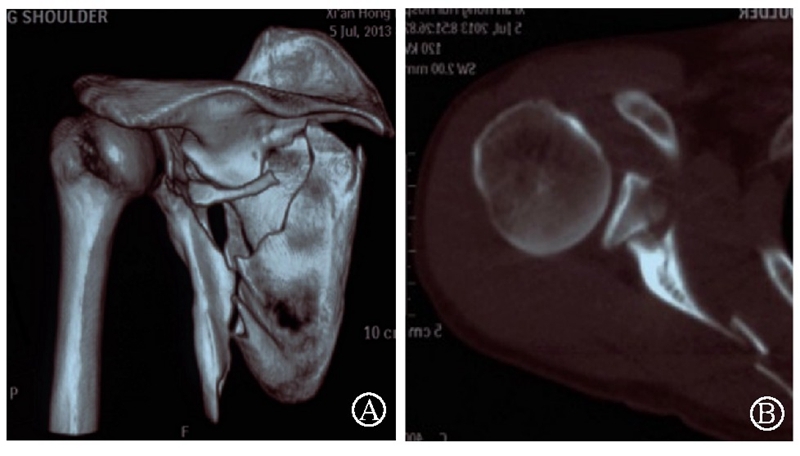

病例4为53岁男性患者,因高处坠落导致右肩胛骨骨折,合并右侧第3、5、7、8肋骨骨折(图20-21)。

图20 术前X线片示肩胛颈及肩胛骨体部骨折

图21 术前CT三维重建示肩胛颈及肩胛骨体部骨折 图A:肩胛骨前面观;图B:肩胛骨侧面观

术中采用钢板固定肩胛颈内下方骨折块,肩胛骨体部骨折固定采用缝线辅助固定技术,骨折端以Nice结固定。术后CT三维重建显示骨折复位满意,固定良好(图22)。